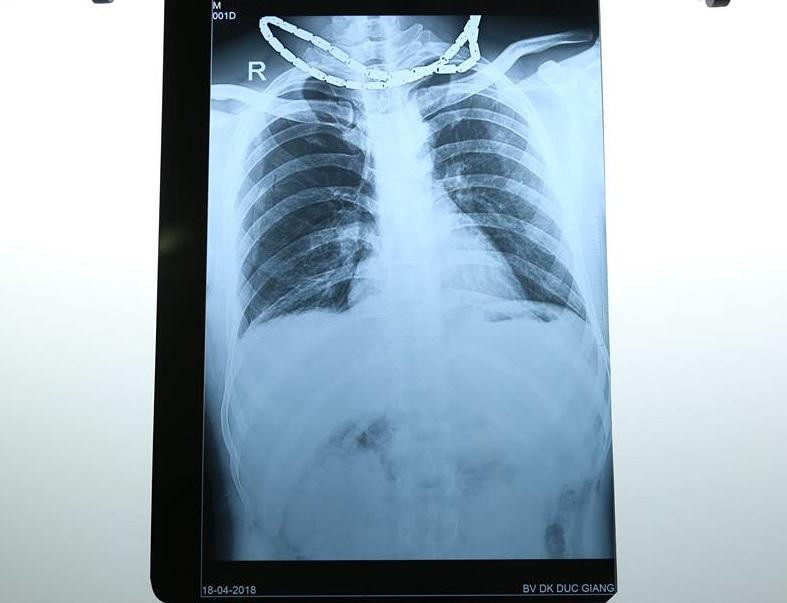

Bác sĩ cho biết, bệnh nhân nhập viện có khoảng 4 vết thương sau vai phải, khoang liên sườn 10, 11 phải, mặt trước ổ bụng (P) cách gai chậu trước trên khoảng 5cm, vết thương thấu ổ bụng. Phim X-quang lồng ngực có tràn khí, tràn máu màng phổi bên phải.

Hình chụp X-quang, bệnh nhân có nhiều vết thương thấu ngực, thấu bụng.

Chẩn đoán bệnh nhân bị đa vết thương, vết thương thấu phổi bên phải, vết thương thấu bụng. Bệnh nhân nhanh chóng được chuyển lên phòng mổ để phẫu thuật cấp cứu xử lý vết thương thấu bụng.